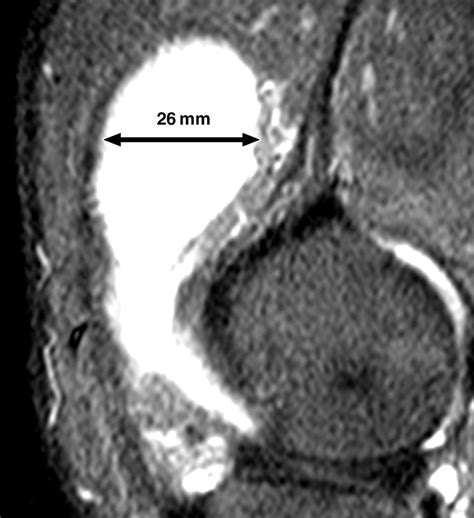

Diagnosing Joint Effusion Knee

Diagnosing joint effusion knee typically involves a combination of physical examination and diagnostic tests. The healthcare provider will:

• Ask about the patient's medical history and symptoms.

• Perform a physical examination of the knee, checking for swelling, tenderness, and range of motion.

• Order diagnostic tests, such as X-rays, MRI, or ultrasound, to visualize the joint and surrounding structures.

• Perform a joint aspiration, where a small amount of fluid is removed from the knee joint using a needle. This fluid can be analyzed to determine the cause of the effusion.